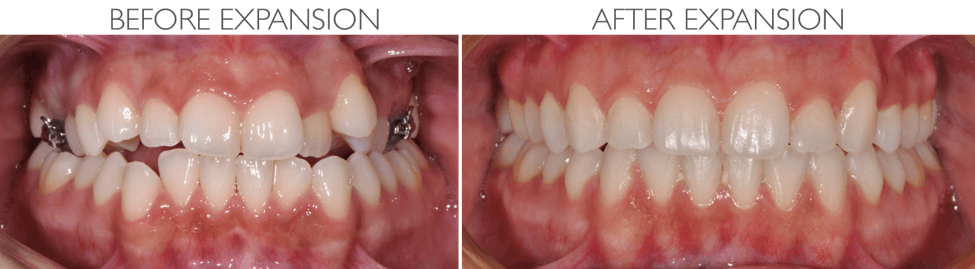

CUSTOM MARPE FOR MATURE PATIENTS

For teens and adults with underdeveloped upper jaws or airway concerns, Dr. Bockow offers custom MARPE (Miniscrew-Assisted Rapid Palatal Expansion). Unlike traditional expanders, MARPE uses precise digital planning and bone-anchored expansion to achieve results even after growth is complete.

- Widen the upper jaw and improve nasal airflow

- Reduce crowding and crossbites

- Enhance facial symmetry and bite function

- Support airway and breathing improvements

Each MARPE is customized to the patient’s anatomy for maximum comfort and effectiveness. Because of this expertise, patients frequently travel from across the country for Dr. Bockow’s specialized treatment.